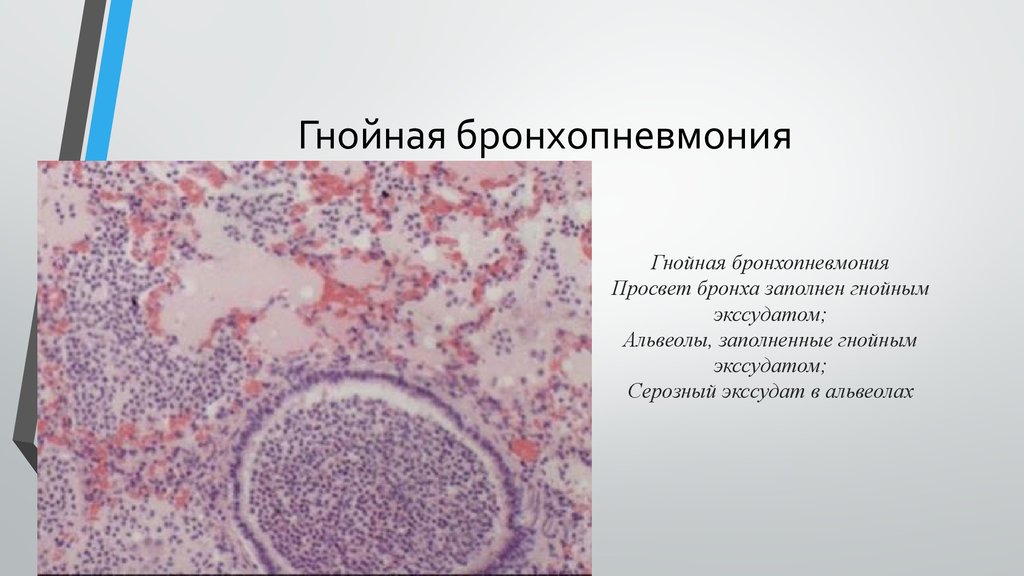

Карнификация Легкого: Микропрепараты и Диагностика

Раздел: Калейдоскоп образов